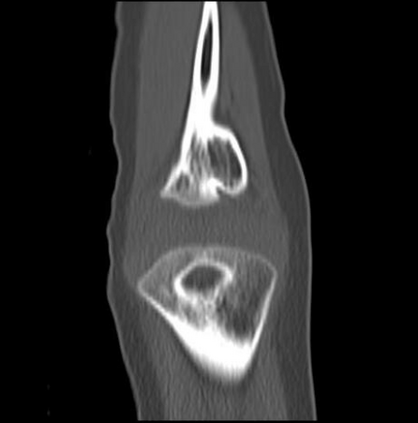

In this study, we aim to initiate the development of Radiology Foundation Model, termed as RadFM.We consider the construction of foundational models from the perspectives of data, model design, and evaluation thoroughly. Our contribution can be concluded as follows: (i), we construct a large-scale Medical Multi-modal Dataset, MedMD, consisting of 16M 2D and 3D medical scans. To the best of our knowledge, this is the first multi-modal dataset containing 3D medical scans. (ii), We propose an architecture that enables visually conditioned generative pre-training, allowing for the integration of text input interleaved with 2D or 3D medical scans to generate response for diverse radiologic tasks. The model was initially pre-trained on MedMD and subsequently domain-specific fine-tuned on RadMD, a radiologic cleaned version of MedMD, containing 3M radiologic visual-language pairs. (iii), we propose a new evaluation benchmark that comprises five tasks, aiming to comprehensively assess the capability of foundation models in handling practical clinical problems. Our experimental results confirm that RadFM significantly outperforms existing multi-modal foundation models. The codes, data, and model checkpoint will all be made publicly available to promote further research and development in the field.